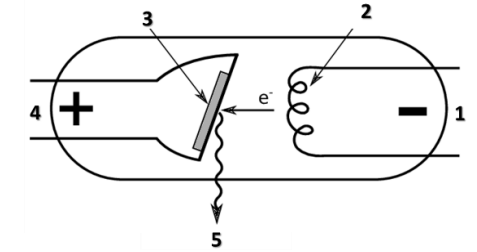

Observe o esquema a seguir representando uma ampola radiográfica.

No esquema, quais são as áreas indicadas pelos números 1, 2, 3, 4 e 5 respectivamente?